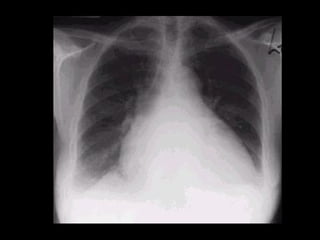

CARDIOMEGALIA  Mayor de 0.5 es sugestivo de cardiomegalia.  Índice Cardiotorácico   ICT =  A + B ________  C C B A

CARDIOMEGALIA Mayorde 0.5 es sugestivo de cardiomegalia. Índice Cardiotorácico ICT = A + B ________ C C B A